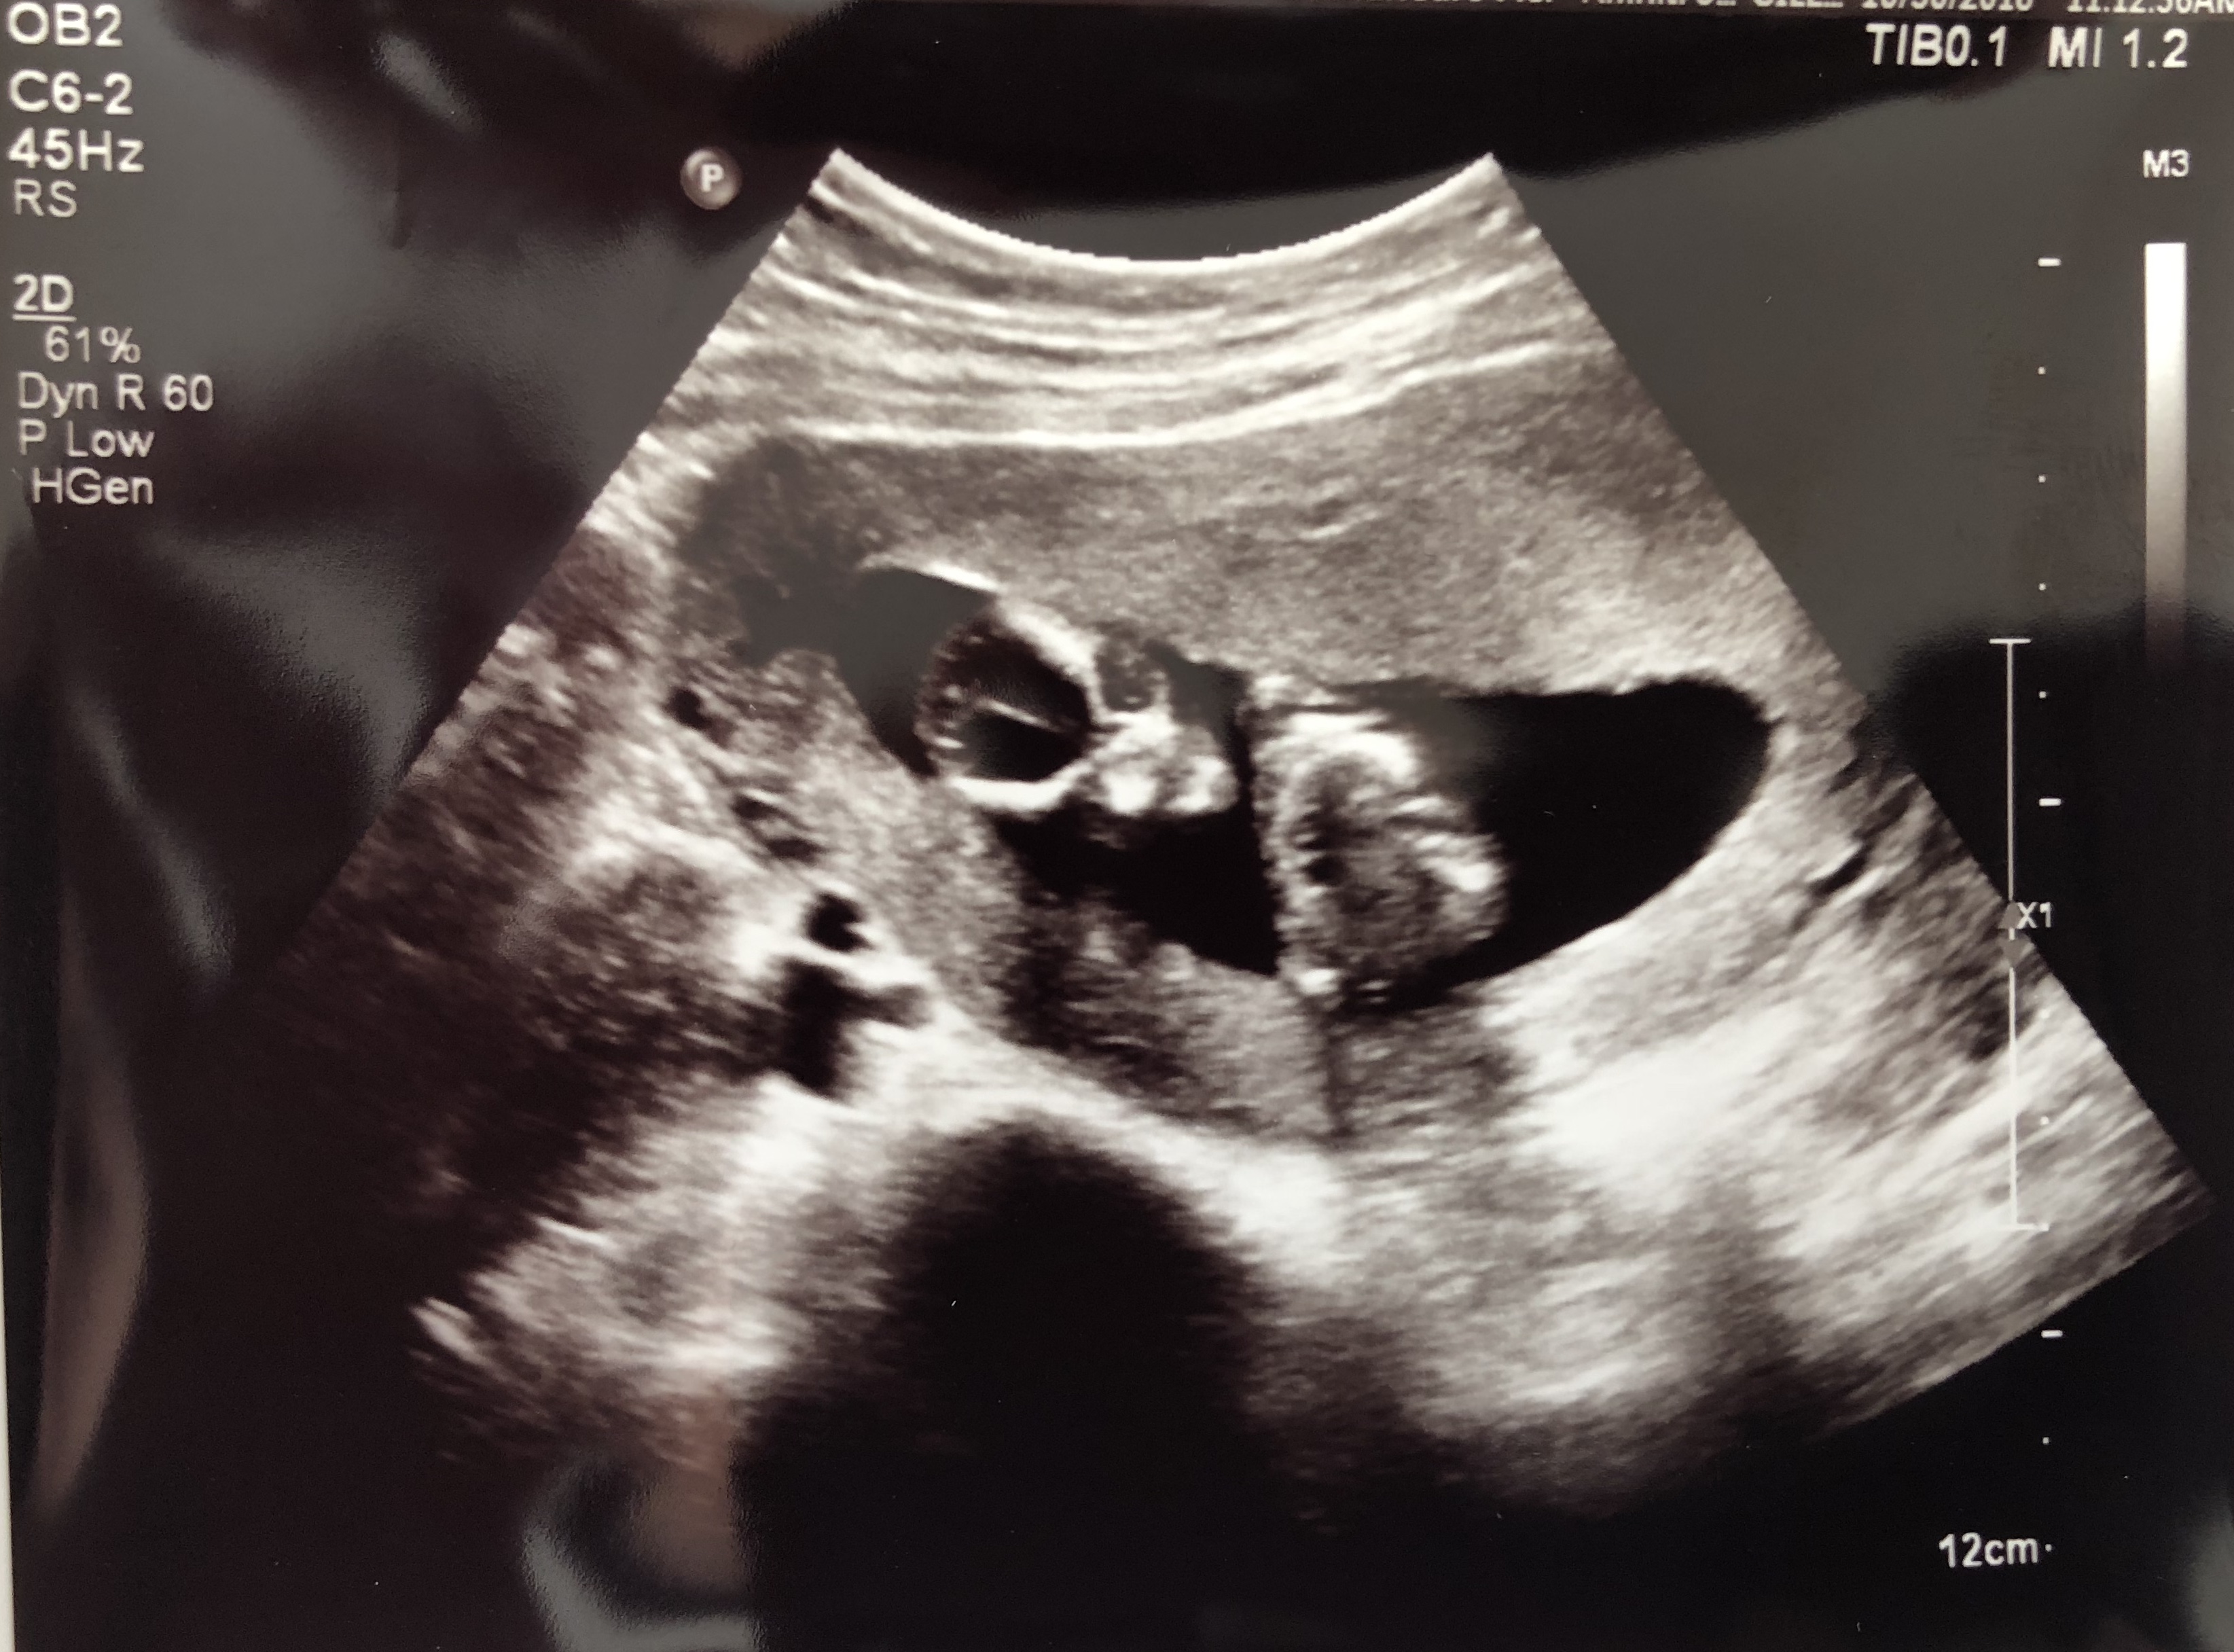

Can anyone guess my baby gender by skull theory?

14w

Attachment 40782